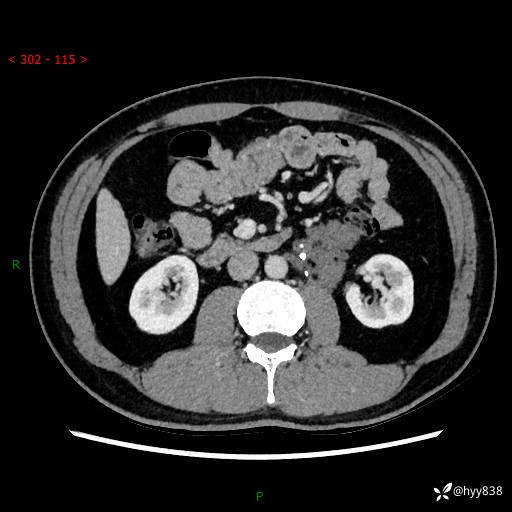

现病史:患者3月余前检查发现左侧腹膜后占位,大小约3.7*4.9cm,平素无腰疼,无肉眼血尿,无尿频尿急等不适,当时未特殊处理,在门诊复查CT提示左侧腹膜后占位,门诊拟“左侧腹膜后占位”收入院。 起病以来,患者精神佳,饮食、睡眠良好,大小便正常,体力体重无明显变化。

腹膜后CT平扫+增强